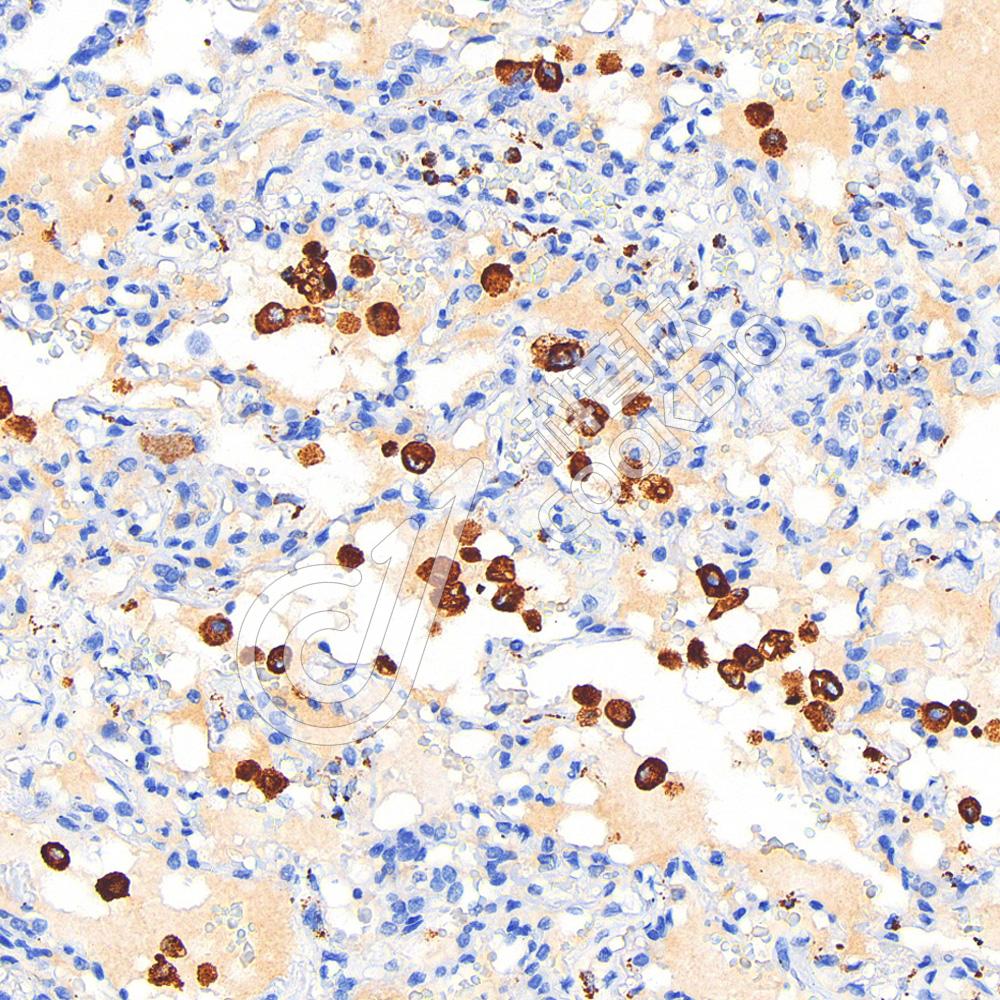

IHC检测CD68蛋白(货号 K1347169).

样品: 人肝癌, 4%多聚甲醛 (货号KSG1101) 固定12-24小时.

抗原修复: Tris-EDTA抗原修复液(pH 9.0) (KSG1203), 98℃, 20分钟.

—抗: 1: 600稀释, 4℃ 孵育过夜.

二抗: S-vision免疫组化多聚二抗(山羊抗兔),即用型 (货号KB3906), 室温孵育20分钟.

样品: 人肺癌, 4%多聚甲醛 (货号KSG1101) 固定12-24小时.